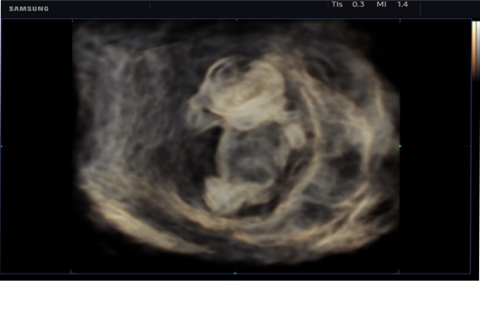

CrystalVue™ is an advanced volume rendering technology that enhances visualization of both internal and external structures in a single rendered image using a combination of intensity, gradient and position